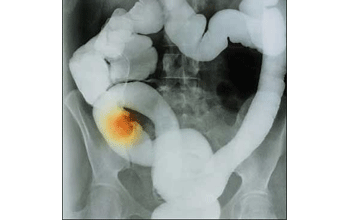

Son múltiples las advertencias que se han hecho respecto a los graves daños a la salud provocados por la obesidad, el problema mayor es que cada vez son más graves las enfermedades asociadas al exceso de peso destacándose el cáncer de colon y recto que se ha convertido en una de las causas de muerte entre personas de los 45 a los 64 años.

El crecimiento de esta enfermedad es exponencial y en este año se considera ya como un problema de salud pública. En la década de 1998 a 2008 creció el número de casos de cáncer de colon y recto en un 69 por ciento, al pasar de mil 605 a 2 mil 525 pacientes, sobre todo en la edad productiva de 45 a 64 años. De acuerdo con proyecciones realizadas en México, se pronostica que el número crezca a 54 personas diagnosticadas diariamente a finales de 2011.

Así lo advirtió la doctora Elizabeth Escobar, Oncóloga del Instituto Nacional de Ciencias Médicas y Nutrición Salvador Zubirán, explicó que la alta mortalidad es propiciada, principalmente, por un mal diagnóstico o un diagnóstico tardío y los síntomas más frecuentes incluyen hemorragia rectal, cambios en las defecaciones y dolor abdominal. La presencia de síntomas notables o la forma en que se manifiestan depende un poco del sitio del tumor y la extensión de la enfermedad.